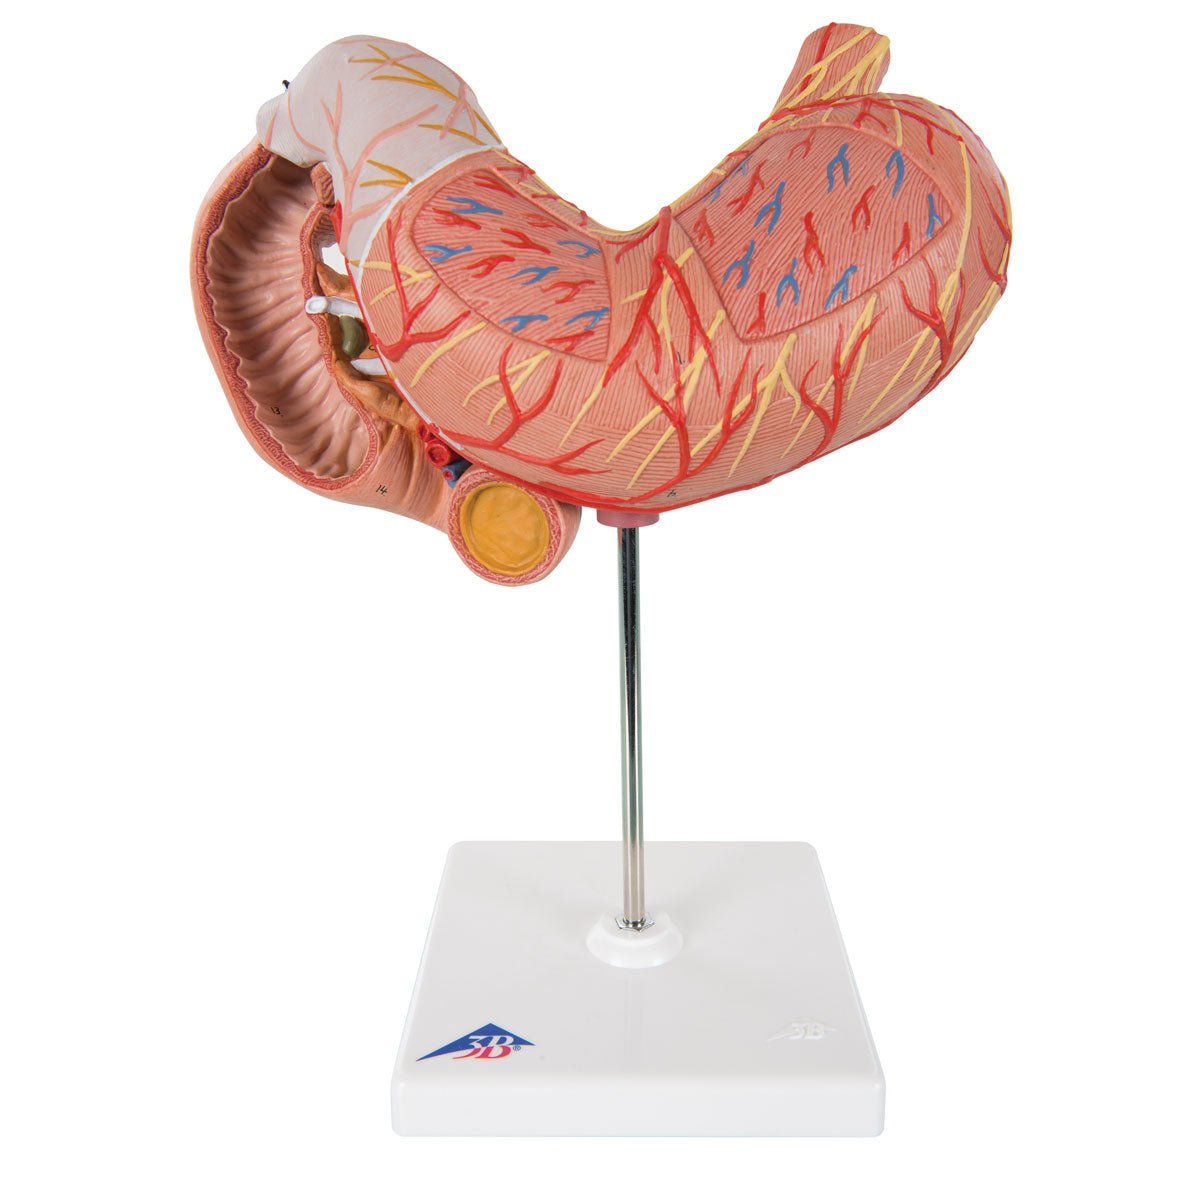

Salg af anatomiske modeller er det bærende element i eAnatomi, selvom vi også bruger mange ressourcer på at udvikle vores egne anatomiske materialer som fx plakater. Anatomiske modeller anvendes til forskellige formål og kan både vise afgrænset væv, organer samt organsystemer. Søger du en simpel model af knoglevæv eller måske en avanceret torso-model baseret på MRI teknologi, kan du finde det hele på eanatomi.com.